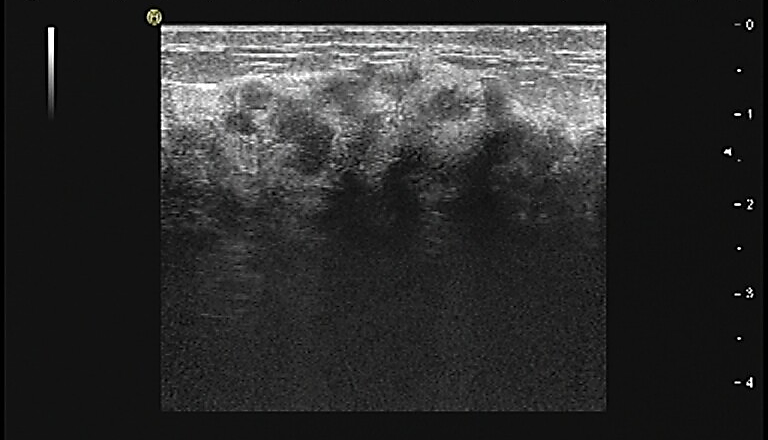

乳腺彩超提示左乳上方及外侧软组织水肿明显,上方10-3点距乳头2cm探及低回声,大小无法测量,深34 mm,形态不规则,边界不清晰,边缘毛刺,内部回声不均匀,后方回声衰减,后方胸大肌显示不清晰,彩色血流条状,RI 0.57。左侧腋下探及多个椭圆形中低回声区,大者约15*12 mm,边界尚清晰,淋巴门结构不清晰,彩色血流条状。BI-RADS 4B(图1)。

图1.乳腺彩超(左:乳腺;右:腋窝淋巴结)